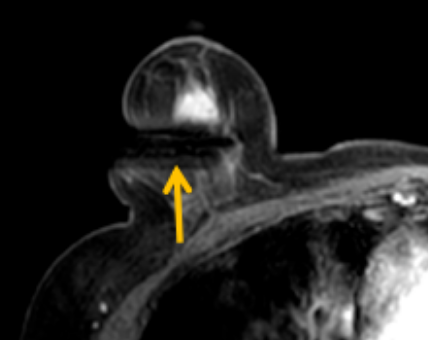

陳寶瑩評(píng)估圖像后發(fā)現(xiàn)病變?yōu)閮H僅在磁共振增強(qiáng)時(shí)顯示,為非腫塊樣病變,比較散,必須取得足夠多的組織才能確保病理檢查的準(zhǔn)確性,常用的核芯針活檢獲取的組織較少,因此最終確定了磁共振引導(dǎo)下行真空輔助抽吸旋切活檢。取得患者及家屬認(rèn)可后,陳寶瑩帶領(lǐng)團(tuán)隊(duì)開(kāi)始進(jìn)行術(shù)前準(zhǔn)備。

針對(duì)患者乳房小固定難度大這一問(wèn)題,陳寶瑩通過(guò)巧妙體位和固定器的調(diào)整,順利固定好乳房。經(jīng)過(guò)磁共振多模態(tài)掃描,陳寶瑩找出病變活性成分相對(duì)集中區(qū)域,精準(zhǔn)確定穿刺路徑,置入引導(dǎo)針、旋切針,到位后多角度旋切取出足量組織,拔除旋切針后即時(shí)行磁共振掃描,精準(zhǔn)取得組織且術(shù)區(qū)出血很少,遂加壓包扎,整個(gè)過(guò)程非常順利,旋切活檢后患者回家休息。兩天后隨訪,李女士沒(méi)有任何不適,五天后皮膚上幾毫米的小切口已經(jīng)愈合。最終病理結(jié)果證實(shí)為乳腺導(dǎo)管原位癌,為早期乳腺癌,為患者后續(xù)針對(duì)性治療奠定了基礎(chǔ)。